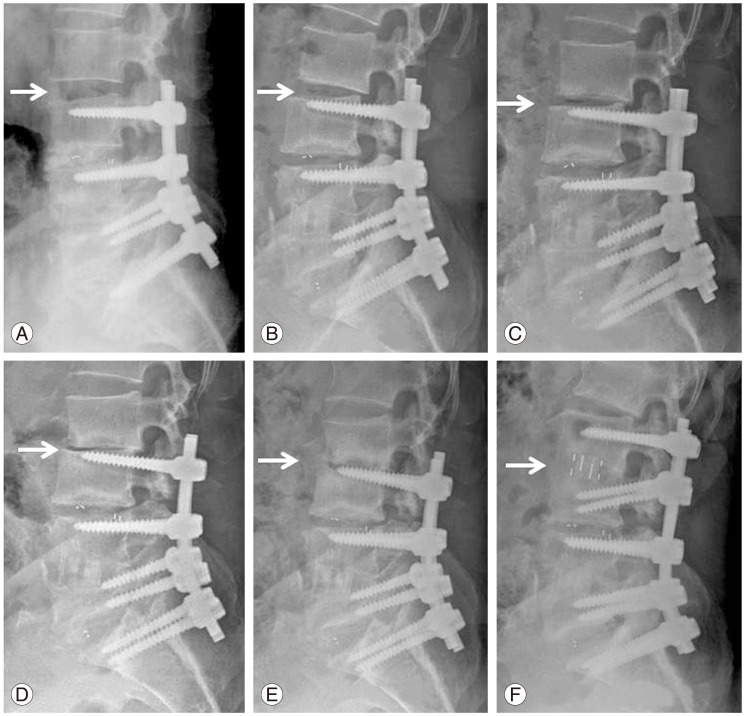

Progressive settling, development of retrolisthesis, and segmental kyphosis was gradually developed in the adjacent segment during follow-up. The patient was treated by minimally invasive direct lateral interbody fusion of the adjacent segment and posterior extension of fusion. Postoperative (A) 3 months, (B)6 months, (C) 9 months, (D) 12 months, (E) 18 months, and (F) after revision.